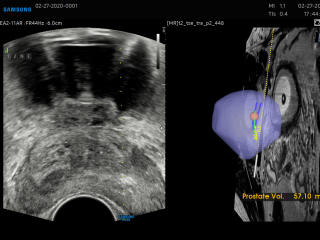

Die Ultraschalldiagnostik ist in allen Bereichen der Medizin eine der wesentlichen Säulen der bildgebenden Diagnostik und ist ein essentieller Bestandteil der täglichen Routine. Diese bildgebende Technik gehört zu der am schnellsten wachsenden Verfahren in der Medizin. Der medizinische Ultraschall, liefert in vielen Bereichen beeindruckende Fortschritte und führt zu einer Steigerung des aktuellen Wissens über moderne Diagnose- und Interventionstechniken. Für eine optimale Vorbereitung auf diesen Entwicklungstrends, Bedarfs es einer kontinuierlichen Aus- und Weiterbildung.